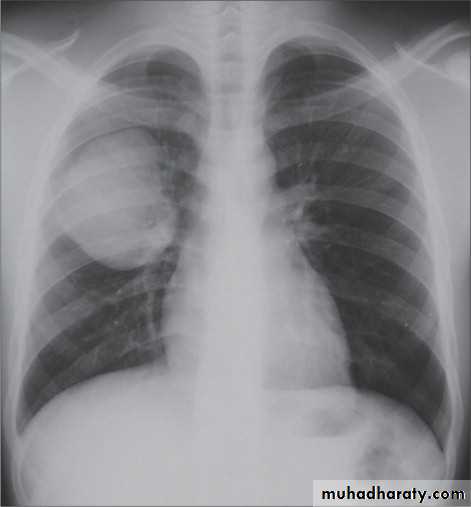

Hydatid cysts result from infection by the Echinococcus, and can result in cyst formation anywhere in the body. Humans are accidental host and the infection occurs by ingesting food contaminated with Echinococcus eggs ,Pulmonary hydatid infection is a common manifestation of hydatid disease.The lung is the second most common site of involvement with echinococcosis granulosus in adults after the liver (10-30% of cases), and the most common site in children. The coexistence of liver and lung disease is present in only 6% of patients .

Chest XR features include :

Non-complicated hydatid

multiple or solitary rounded opacity

diameter of 1-20 cm

unilateral or bilateral

predominantly found in the lower lobes

Complicated cysts may show:

meniscus sign or air crescent sign

cumbo sign or onion peel signThe onion peel sign (also called the cumbo sign) is a feature seen with complicated pulmonary hydatid cyst in which air lining between the endocyst and pericyst has the appearance of an onion

water-lily is seen in hydatid infections when there is detachment of the endocyst membrane which results in floating membranes within the pericyst that mimic the appearance of a water lily.

consolidation adjacent to the cyst (ruptured cyst)

Simple HC Ruptured HC